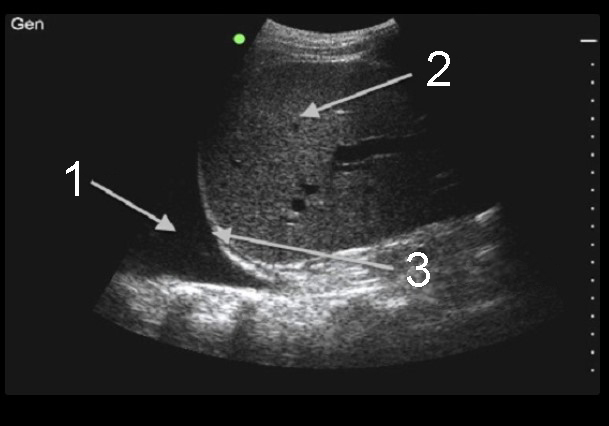

胸腔穿刺胸腔积液右上腹 (RUQ) 2 图像

流体(胸腔积液)

肺部

膈膜